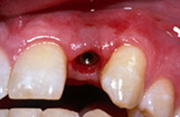

Поставянето на зъбни импланти е рутинна дейност в нашата практика. То се извършва след предварително рентгенологично изследване и внимателно планиране. Имплантирането се извършва гарантирано безболезнено под местна упойка, но при страхливи пациенти по тяхно желание може да бъде и под обща упойка. Поставянето на зъбен имплант (присаждане на зъб) е по-малко травматично за пациента от изваждане на зъб.

За период от 2 до 6 месеца зъбният имплант се интегрира в костта, след което се пристъпва към поставяне на необходимата конструкция - коронка, мост или протеза. Днес има и импланти, които по преценка на лекуващия лекар се натоварват веднага – т.е. не се изчаква имплантатът да се интегрира, а веднага след поставянето му се слага коронката.